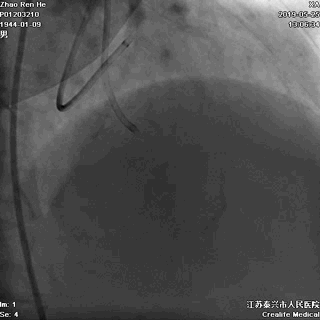

一、冠状动脉造影

右冠几乎齐根闭塞

右向左无侧枝循环

二、双侧冠状动脉造影(1周后)

RCA几乎齐根闭塞,非锥形残端

闭塞入口处有分支发出

闭塞出口处发出分支血管

CTO闭塞段长度小于20mm